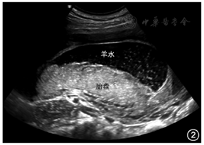

羊水内可见多发的颗粒样或小片状高回声,可随胎儿的运动或外力挤压而缓慢移动,呈"飘雪样",见图2。孕早期或孕中期发现胎儿露脑畸形、无脑畸形、羊膜带综合征等严重胎儿畸形时,可出现这种类型的强回声,多为破碎的胎脑组织、其他组织或出血漂浮于羊水中所致,出现所谓的"牛奶样羊水"[9,10];尤其是在孕妇侧动体位或胎动时更为明显。孕妇有阴道流血时,临床上也可观察到这种羊水回声增强,可能与合并羊膜腔内出血有关。羊膜腔内出血可为行绒毛穿刺取样术、羊膜腔穿刺术、经皮脐血穿刺术、宫内输血的并发症,是早产或死胎的高风险因素[11,12]。此外,当出现绒毛膜下出血及胎盘早剥时,也可出现羊膜腔内出血[12]。国外有病例报道,胎儿消化道出血也可出现羊水回声增强的超声表现[13,14,15]。